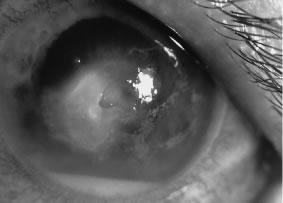

In the early stages of infection, filamentous fungi produce signs that are readily distinguishable from yeast or bacterial keratitis. The most distinctive sign is the presence of delicate, fine, feathery, opalescent, gray-white or yellow-white material in the anterior stroma, surrounded by scant cellular infiltrate or edema (Fig. 1). The epithelium may be intact. The overlying epithelium may be granular and the surface elevated and irregular in contour. Linear infiltrates typically extend into the adjacent stroma. Multiple discrete opacities may develop outside the perimeter of the principal focus of inflammation, either separated by clear stroma or linked by fine linear collections of inflammatory cells and material (Figs. 2 and 3). In the absence of inflammation in the adjacent stroma, branching hyphal fragments may be visualized by biomicroscopy (Figs. 4 and 5). Confocal microscopy may also detect hyphal elements within the stroma.28,29 Peripheral infection resembles noninfectious marginal infiltrative and ulcerative keratitis (Fig. 6). Multifocal keratitis may develop after contact lens wear or injury by multiple projectiles (Fig. 7). In the early stages, iritis is present and the intraocular pressure remains normal. Inappropriate, empirical therapy of fungal keratitis with topical fluoroquinolone or aminoglycoside antibiotics may suppress or eliminate the superficial elements but allow extension of the organisms into the stroma because these agents may possess selective antifungal activity.4,30,31

There is no distinguishing clinical sign by which to recognize the genus or species of the infectious filamentous fungus. F. solani is the most virulent organism and typically produces rapidly progressive infection characterized by epithelial and stromal ulceration, dense stromal necrosis, abundant cellular infiltrate, and edema in the adjacent stroma and hypopyon (Figs. 8 and 9). Delicate feathery components are transient. Individual hyphal fragments are rarely visualized. Infection by certain species of Aspergillus and Scedosporium (Figs. 10 and 11) resembles F. solani keratitis and progresses rapidly. Infection by less virulent organisms, such as Curvularia and Alternaria species, produces small, focal (less than 3-mm diameter) areas of nonnecrotizing stromal inflammation with delicate feathery borders (see Fig. 1 and Fig. 12). Macroscopic pigmentation may develop in keratitis caused by Alternaria, Curvularia, and other dematiaceous fungi (Fig. 13).4,11,14 The central component may progress to dense, opaque, gray-white suppuration in the deep stroma without enlargement in total area and may be accompanied by mild inflammation in the adjacent stroma. Iritis is minimal to moderate. Infection caused by other, relatively less virulent organisms resembles herpes simplex or noninfectious keratitis (Fig. 14).